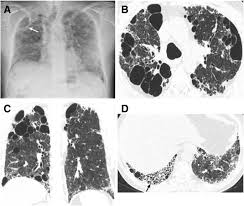

The Stages Of Pulmonary Sarcoidosis What Do They Really Mean Foundation For Sarcoidosis Research from www.stopsarcoidosis.org Emphysema does not, however, lead to lung cancer. In the united states, trends in lung cancer tend to follow trends in cigarette smoking. Lung cancer develops due to the overgrowth of. Chronic obstructive pulmonary disease (copd) is a serious lung condition found mostly in smokers. If the condition is misdiagnosed or its symptoms are ignored, a patient may not receive appropriate treatment until the cancer has progressed to an advanced stage. When sarcoidosis affects the lungs, symptoms can mimic idiopathic pulmonary fibrosis including shortness of breath and a dry cough. Pneumonia is a lung infection that leads to breathing difficulties and fluid in the lungs. Malignant tumors trigger inflammation in surrounding normal lung tissue, and they may obstruct your airways and interfere with normal airflow.

Stereotactic Body Radiation Therapy For Early Stage Non Small Cell Lung Cancer A Primer For Radiologists Radiographics from pubs.rsna.org Having copd may put you at risk for lung cancer and heart disease, among other conditions. This is because smoking complications can extend from lung tissue damage (emphysema) to lung cell damage (cancer). When cancer begins in the cells of the lung it is known as primary lung cancer. Various viruses, bacteria, and fungi can cause pneumonia. Lung cancer is a general term that includes all abnormal lung tissue cells that multiply unregulated and form tumors or growths in the lungs.these tumor cells may spread (metastasize) to other parts of the body.; In lung cancer, lung cells exhibit abnormal and uncontrolled growth starting the lungs, while asthma is caused by inflammation and/or mucus that decreases or blocks the breathing passages (bronchioles) of the lungs. Although slipping from emphysema to copd is usually not a drastic decline in health, early detection of lung cancer is critical for increasing your treatment options and improving your prognosis. Initial reports of an association between lung cancer and emphysema date back to the 1950s, when a report on 10 patients with congenital cystic pulmonary emphysema who died from primary lung cancer was published (4).

Tuberculosis Mimicking Lung Cancer Sciencedirect from ars.els-cdn.com This can lead to misdiagnosis as conditions such as irritable bowel syndrome (ibs). This might be the reason your cancer risk goes up with age (the median age for a lung cancer diagnosis is 66). Lung cancer and emphysema are not the same things. Copd is a term used for a group of obstructive lung diseases. While both lung cancer and emphysema can be caused by smoking or exposure to dangerous substances, they cause different problems in the lungs and require different treatments. The relationship between these diseases is instead one based upon mutual risk factors, namely smoking. That's because the symptoms of emphysema can easily conceal copd, and copd can conceal the presence of lung cancer. Pancreatic cancer may also be misdiagnosed as gallstones or pancreatitis, or the inflammation of the pancreas.